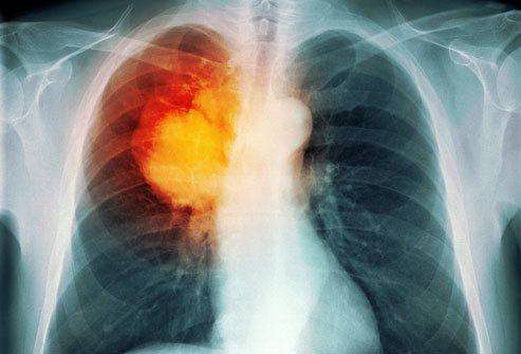

肺癌分为两大类,小细胞肺癌和非小细胞肺癌,针对较常见的非小细胞肺癌而言,医学界将之分为四期,第一、二期的肺肿瘤仍集中于同一面肺部,但当肿瘤入侵至另一边肺部的淋巴结,便属第三期;若扩散至身体其他器官,如常见的骨骼及肝脏,即属第四期。

肺癌多年来是本港的头号癌症杀手,而期数越后,患者的存活率便越低,尤其是第四期肺癌患者,因肿瘤已扩散至肺部以外的器官,医生可用的治疗方案十分有限,被一般人视之为绝症。